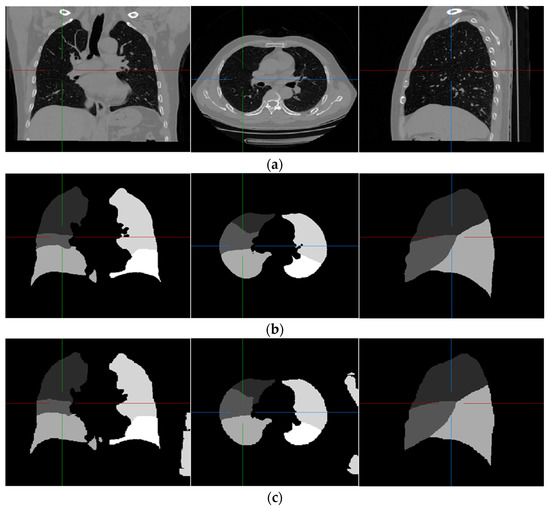

Examples of pulmonary lobe segmentation are shown in Figure 4 and Figure 5 for qualitative visualization. In Figure 4, a case with a general morphology of the lung is presented. In Figure 5, a case with morphological specificity is selected.

Figure 4.

An example of the results of the experiment. (a) Original scan; (b) ground-truth; (c) FRV-Net; and (d) proposed method.

From Figure 4 and Figure 5, it is easy to observe that the results of the FRV-Net are interfered with by the false identification in the background. Additionally, there are irrational holes in the segmented lobe of the FRV-Net. Figure 4 shows that the proposed method could obtain a comparable segmentation result with the FRV-Net method. While in cases with large anatomical differences in the training dataset, the proposed method could avoid a wide range of misclassifications, owning to the aid of the fissures (see Figure 5).

The dice coefficient of the revised FRV-Net method is significantly improved for the left upper lobe. Even compared with the revised FRV-Net method, the result of the proposed method is competitive. Furthermore, the proposed method could prevent interference from the pathological changes in morphology and avoid unreasonable holes in the segmented lobes. Generally, the proposed method could segment the pulmonary lobes accurately and robustly.